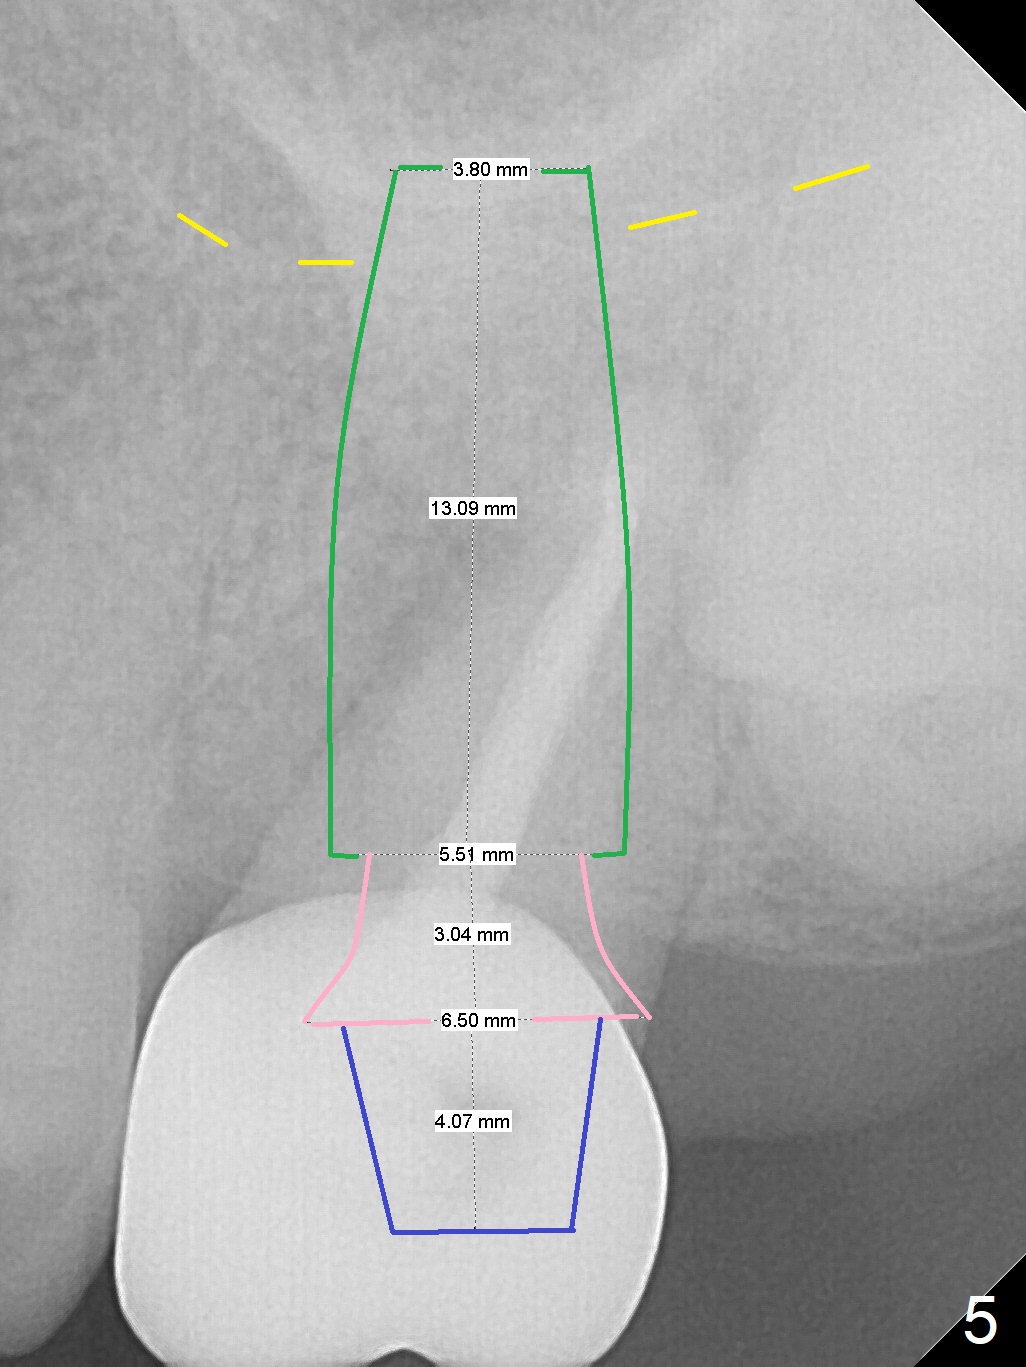

Osteotomy in Mesial Slope A 64-year-old woman will return for extraction/implant for the upper left 2nd molar with a fistula (Fig.1). Since the roots deviate distal (Fig.2 after extraction), initiate osteotomy in the apical 1/3 of the mesial slope with 1.5 mm drill (Fig.3). Once the lamina dura is penetrated, change trajectory (Fig.4) and extend depth for 15 mm (gingival level). After use of 2 mm drill, insert marked parallel pin for PA. The final implant as well as abutment is shown in Fig.5. Return to